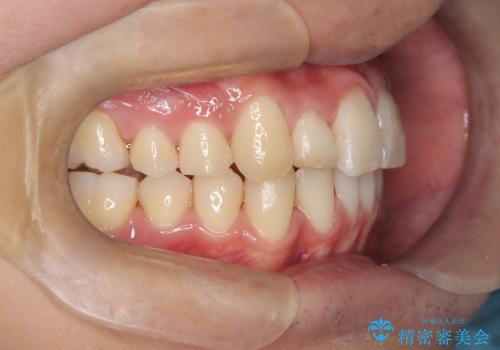

前歯のガタガタを治したい。

- 凸凹を治したいと来院された患者様です。

インビザラインにて、遠心移動を行いながら綺麗に配列することができました。